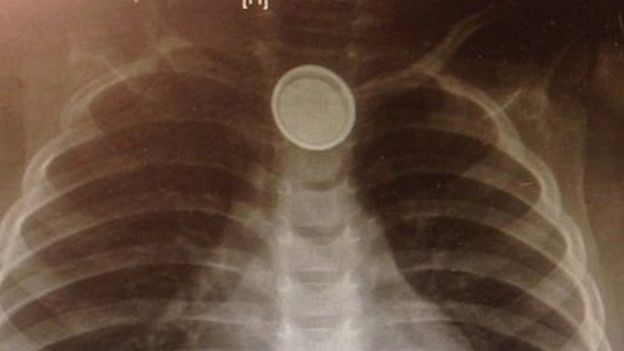

Dhagaxa saacadaha ama ku Jira alaabaha ayaa gubey kadibna dalool u yeelay ilmoyar oo laba Jira kadib markii aan waalidku ka taxadirin oo dhagaxaas uu ka helay guriga dhexdiisa.

Ilmahaas yar ayaa hadda dhagaxaasi gubey daloolna u yeelay hunguriga wuxuuna ku sigtey in uu qarxiyo xidig halbowle ah oo dhiiga u gudbiya maskaxda taas oo keeni lahay dhimasho toos ah.

Ilmaha kore ayaa hadda tuunbo lagu siiyaa cuntada oo dhan kadib markii dhagaxu gubery tuunbada cuntada qaada ee gaarsiisa caloosha.